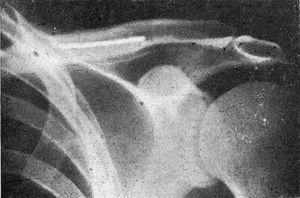

Figura 7. Fractura de clavícula con gran desviación, en la que el enclavijamiento a cielo abierto consigue inmejorables resultados.